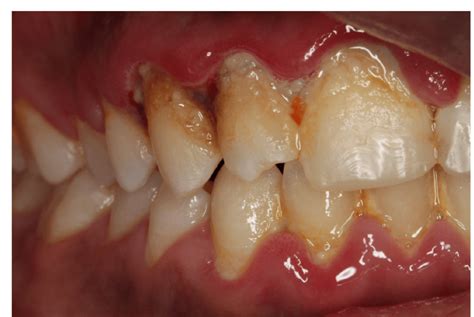

Alright, let’s start with the basics, folks. Acute gingivitis is a sudden, short-term inflammation of your gums. Think of it as your gums throwing a little tantrum – they get red, swollen, and might even bleed a bit when you brush or floss. It’s usually caused by a buildup of plaque, which is basically a sticky film of bacteria that loves to hang out on your teeth. When this plaque isn’t removed properly, those nasty bacteria release toxins that irritate your gums, leading to that inflamed state we call gingivitis. It’s important to distinguish this from chronic gingivitis, which is a more long-term, persistent inflammation. Acute gingivitis often comes on pretty quickly and can be quite uncomfortable if left untreated. Symptoms can include

• Redness : Your gums might look unusually bright red instead of their usual healthy pink.

• Swelling : They can appear puffy and enlarged.

• Bleeding : This is a big one. Gums that bleed easily during brushing or flossing are a classic sign.

• Tenderness : Your gums might feel sore to the touch.

• Bad breath : Sometimes, the bacterial overgrowth can lead to halitosis.

The classic symptoms often include redness and swelling of the gums. Instead of that healthy, firm pink tissue, your gums might look puffy, inflamed, and a vibrant, sometimes angry, red. This is your body’s natural response to irritation and inflammation caused by those pesky bacteria in plaque. Another major indicator is bleeding . If your gums bleed when you brush your teeth, even if you’re being gentle, or if you notice blood after flossing, that’s a big red flag. This bleeding happens because the inflamed blood vessels in your gums become more fragile and prone to rupture. You might also experience tenderness or soreness in your gums. They might feel sensitive to touch, or even just the pressure of eating can be uncomfortable. In some cases, the bacterial overgrowth associated with gingivitis can lead to bad breath (halitosis) . This is because the bacteria are producing volatile sulfur compounds, which we all know as that unpleasant mouth odor. So, if you notice any of these changes, especially if they appear suddenly, it’s definitely worth paying attention to.